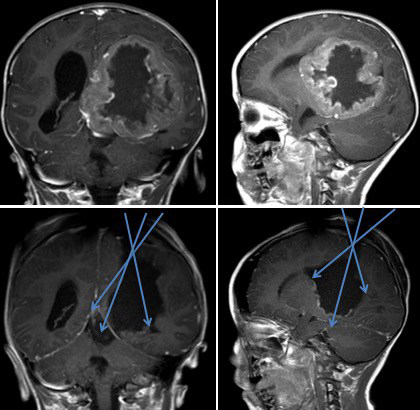

voie trans-temporale - la voie trans-pariétale : en décubitus ventral : pour les tumeurs volumineuses de l’atrium avec extension vers la ligne médiane : permet le contrôle du système veineux profond

voie trans-pariétale

à l’inverse, le carcinome du plexus recrute des pédicules venant de toute la surface du ventricule et le saignement se poursuit jusqu’à la fin de la résection. Il faut surtout être prudent vers la ligne médiane car un saignement du système veineux cérébral interne et de la veine de Galien pourrait être fatal.